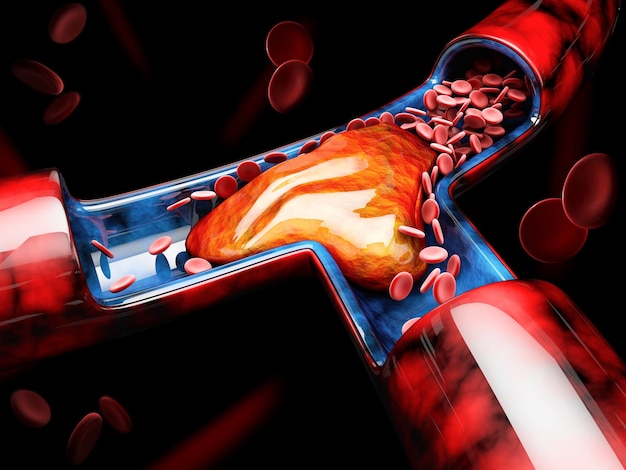

人間の血管の医療静脈血栓の図イラスト画像とPSDフリー素材透過の無料ダウンロード - Pngtree。

動脈硬化、血栓形成。ベクトル医療イラスト。内部の臓器、血栓症、血管内皮のイラスト素材・ベクター Image 61855962。

血栓ができている血管 イラスト素材6665451- フォトライブラリ。

3dイラストで表現された塞栓症と深部静脈血栓症の視覚的描写 写真背景 無料ダウンロードのための画像 - Pngtree。